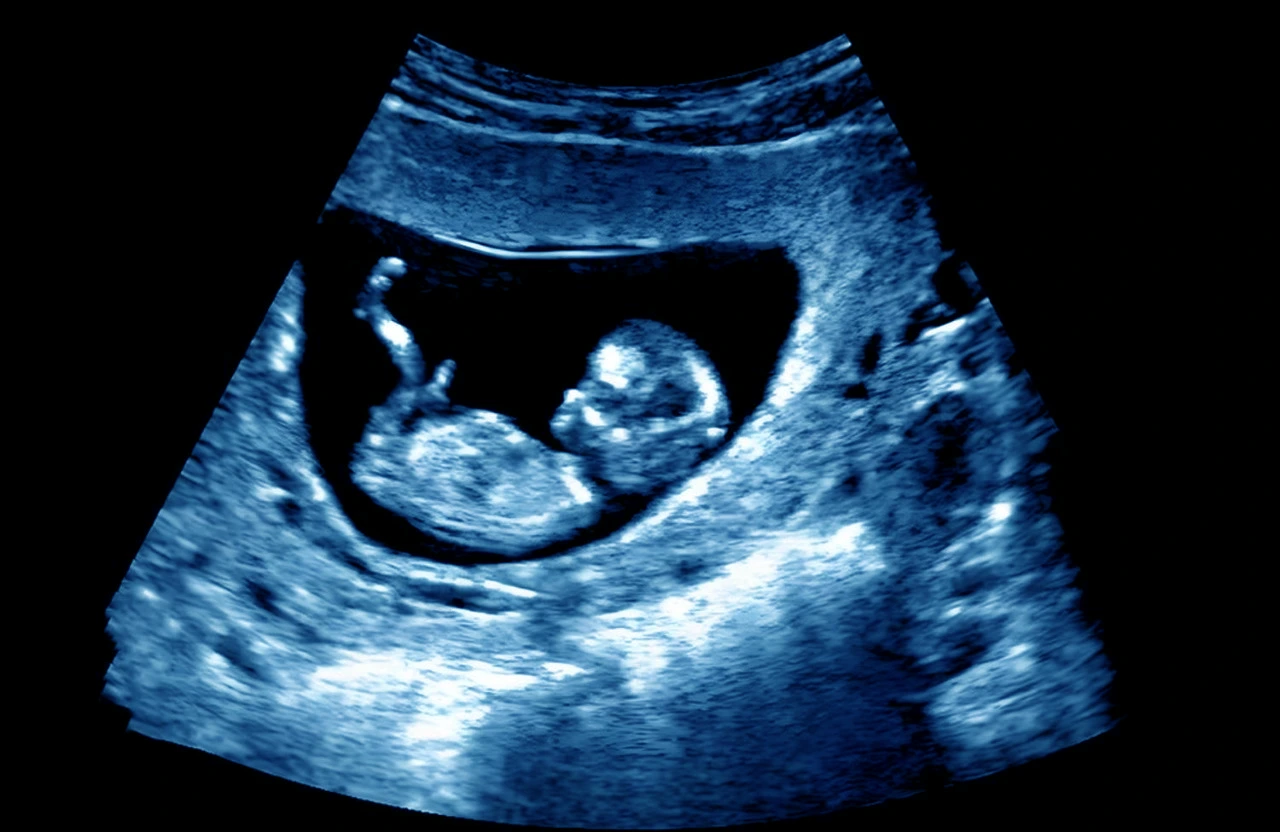

Cuando se identifica una vulnerabilidad, el control de embarazo tradicional se transforma. El objetivo principal es la vigilancia proactiva, utilizando herramientas diagnósticas avanzadas que permiten «ver» el bienestar del bebé con una frecuencia y precisión mucho mayores a las de un embarazo de bajo riesgo.

Ultrasonidos de alta resolución y pruebas genéticas

Dentro de los estudios prenatales especializados, se incluyen los ultrasonidos estructurales detallados y los perfiles biofísicos. Estas pruebas no solo buscan confirmar el diagnóstico de embarazo, sino monitorear el volumen de líquido amniótico y los movimientos fetales. También se pueden realizar pruebas no invasivas de ADN fetal en sangre materna para descartar trisomías, o procedimientos más directos como la amniocentesis si se sospechan malformaciones específicas.